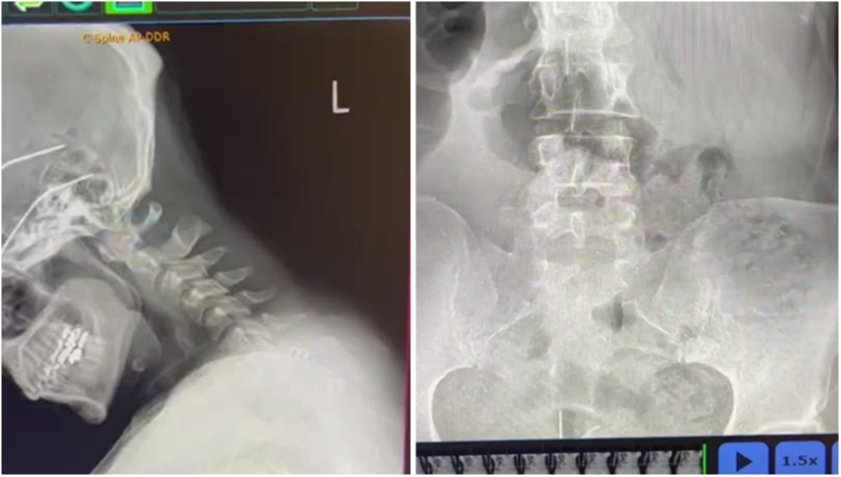

2. DIGITAL SPINAL RADIOGRAPHY

PRS also utilizes static X-ray, to provide precise, spinal alignment studies and rule out pathologies.

By providing a clear baseline for further diagnosis and care, static X-rays enable chiropractors to develop targeted strategies tailored to each patientâs needs.

Serving as the cornerstone for our more advanced technologies and techniques, this method ensures a solid starting point, empowering practitioners to build upon accurate data for optimal spinal correction and lasting patient outcomes.